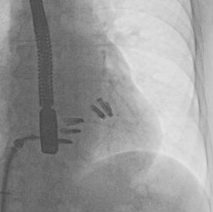

Torrential TR (grade 5)

PA‑mean > 25 mmHg

TRPG < 20 mmHg

TVSL > 40 mm